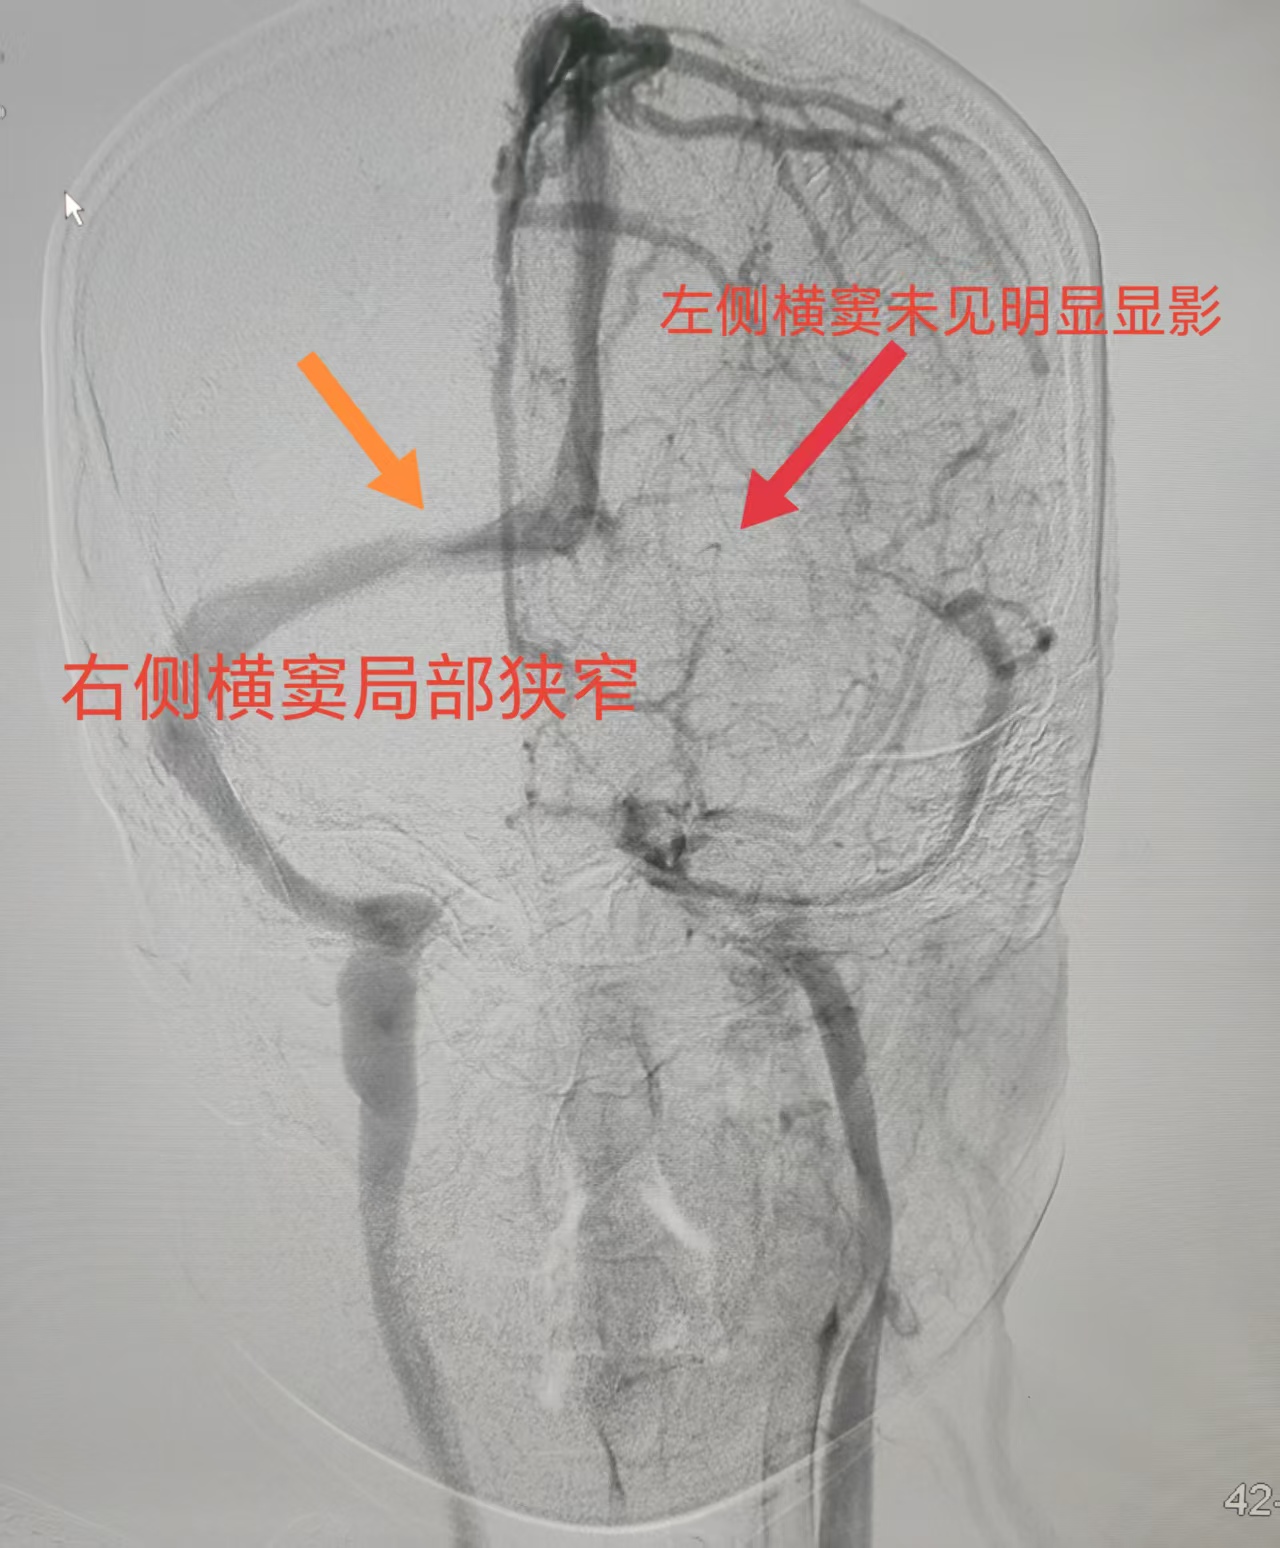

从影像到功能,精准医疗突破诊断瓶颈

三年来,头痛如影随形地伴随着小荀,她试过各种药物和治疗,效果都不理想。王建峰主任团队接诊后,为她安排了系统检查。头颅MRV提示“左侧横窦未见显影,右侧横窦局部狭窄”,腰穿压力高达220mmH₂O,眼底检查也发现双侧视乳头水肿。这一系列线索都指向了一种极容易被忽视的疾病——特发性颅内压增高症,而静脉窦狭窄很可能是其背后的“真凶”。